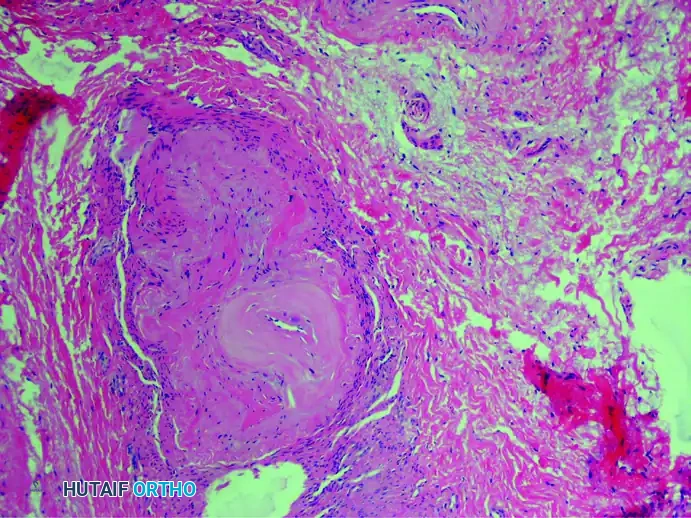

1. Perineural Fibrosis

The interdigital nerve is greatly thickened by dense, concentric layers of perineural fibrous tissue. This fibrosis acts as a constricting scar around the nerve fascicles.

(Hematoxylin and eosin stain demonstrating severe perineural fibrosis)